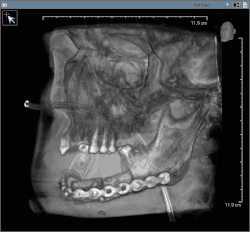

Post-operative image after removal of oral cancer with part of the mandible (feeding tube in nose)